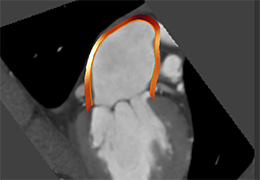

View X-Ray CT & MRI Scans Fast and Easily

Designed for surgeons, Pro Surgical 3D makes it easy to view patient scans quickly. Pro Surgical 3D facilitates the optimal 3D treatment and assessment workflows based on X-ray CT and MRI scans – and best of all, it’s FREE!

Performs 3D reconstruction and volume rendering.

Multi-planar slicing.